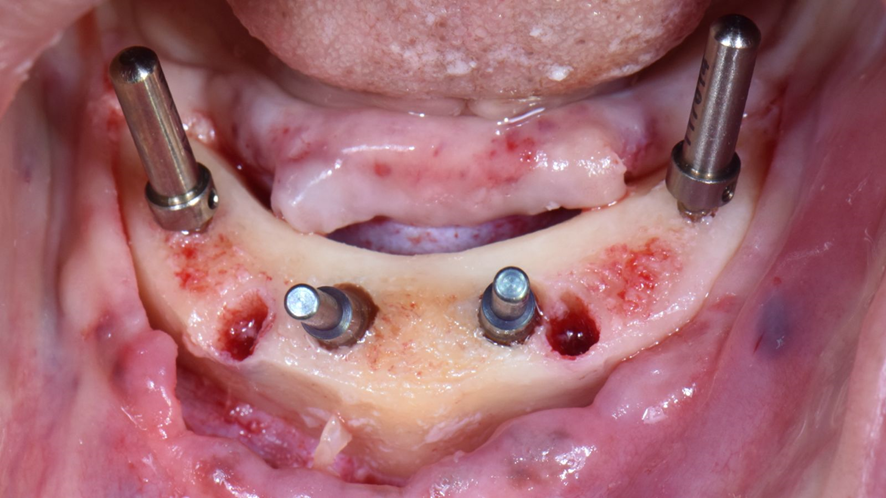

Neste caso clínico foi utilizado o novo corpo de escaneamento para arcos desdentados totais da Implacil Osstem. Os corpos de escaneamento são encaixados no scan body através de encaixes de precisão e são disponibilizados em três tamanhos diferentes (5, 10 e 15mm) para que eles possam ficam próximos entre si e facilitar a leitura pelos scanners intraorais.